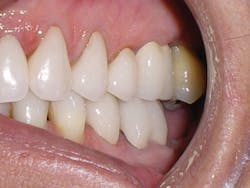

Compare the inclination of the long axis of teeth on #12 before and after treatment.

The six-week follow-up visits with Evin were eye-opening! I had the opportunity to observe his periodontal condition improve at each interval. After 30 aligners, or 15 short months, Evin's clear aligner orthodontic treatment was completed and final photos were taken. His bite was checked to confirm we had achieved our initial goal. Evin now had the appropriate overbite, overjet, and class I occlusion with proper posterior intercuspation with no interferences.

Figure 1